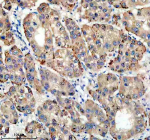

Immunohistochemical staining of TIRAP using anti-TIRAP antibody. TIRAP was detected in a paraffin-embedded section of human liver cancer tissue. Heat mediated antigen retrieval was performed in EDTA buffer (pH 8.0, epitope retrieval solution). The tissue section was blocked with 10% goat serum. The tissue section was then incubated with 2 ug/ml rabbit anti-TIRAP antibody overnight at 4oC. Peroxidase Conjugated Goat Anti-rabbit IgG was used as secondary antibody and incubated for 30 minutes at 37oC. The tissue section was developed using an HRP secondary and DAB substrate.